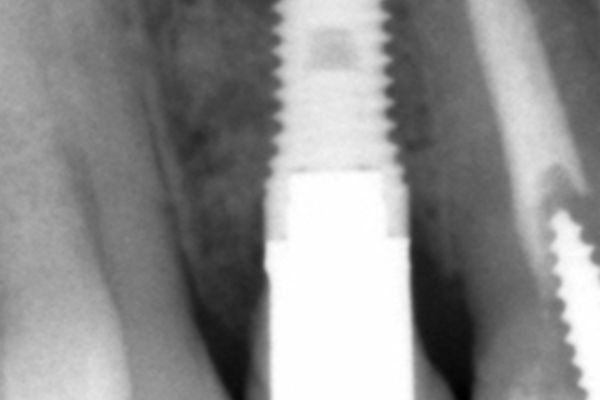

As best clinical case, Garrido Martínez, et al. are the first winners with an excellent clinical case on the maxillary reconstruction of a patient with subperiosteal implants. Anitua repeats the award with a clinical case where they successfully show the explantation of a poorly positioned implant in the aesthetic sector and its subsequent regeneration.